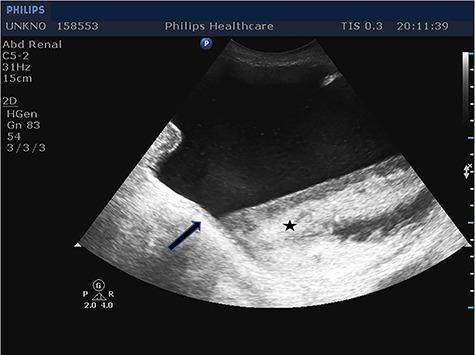

Inguinoscrotal hernia containing the urinary bladder is a rare entity found in 1-4% of inguinal hernias, while patients rarely present symptoms of urinary dysfunction. We present the case of a 79-year-old Caucasian male with acute renal dysfunction and incarcerated inguinoscrotal hernia containing the entire urinary bladder. The patient presented in the surgical emergency department due to an incarcerated right inguinoscrotal hernia and deteriorated renal function. Preoperatively, ultrasound imaging was performed, which showed the presence of the whole bladder in the hernia sac. The bladder was repositioned to its anatomic position and hernia was repaired through a modified Lichtenstein technique. In patients with inguinoscrotal hernia and acute urinary tract symptoms, surgeons should be aware of the possibility of inguinal bladder hernia. Preoperative imaging can help in preventing intraoperative bladder damage.

摘要

包含膀胱的腹股沟阴囊疝是一种罕见的疾病,在腹股沟疝中占1%-4%,而患者很少出现排尿功能障碍的症状。我们报告一例79岁的白种男性病例,该患者患有急性肾功能不全,其腹股沟阴囊疝嵌顿并包含整个膀胱。患者因右侧腹股沟阴囊疝嵌顿及肾功能恶化就诊于外科急诊。术前进行了超声检查,结果显示疝囊内存在整个膀胱。将膀胱复位至其解剖位置,并通过改良的Lichtenstein技术修复疝。对于患有腹股沟阴囊疝和急性尿路症状的患者,外科医生应意识到腹股沟膀胱疝的可能性。术前影像学检查有助于预防术中膀胱损伤。